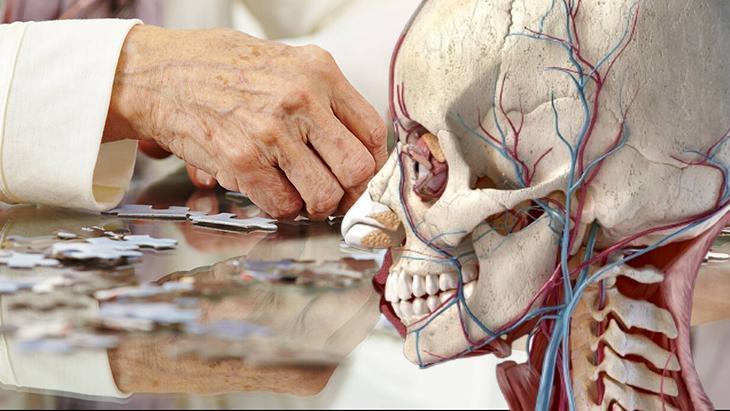

Bunamanın işareti çene kasında gizli! İskeleti küçük olanlar risk altında

Johns Hopkins Tıp Fakültesi'nde yapılan yeni bir araştırmaya göre, kas kütlesi kaybının diğer adıyla sarkopeninin, demans riskini önemli ölçüde artırabileceğine dair veriler elde edildi. Bulgulara göre, belirli bir çene kasının demansla ilgili mesaj verdiği ortaya çıktı. İşte çalışmanın hayret verici detayları.

6 ay boyunca takip edilen katılımcıların gözlem sonucunda çoğunun daha küçük temporalis kasları olduğu ve demans riskiyle burun buruna oldukları görüldü.

Ayrıc daha büyük temporalis kası olanlara kıyasla bilişsel test puanlarında ve beyin boyutlarında daha fazla düşüş tespit edildi.

Araştırmacılar son olarak çene kasının kalınlığı ve büyüklüğü gibi özelliklerinin vücuttaki kas kütlesi hakkında bir fikir verebileceğini dolayısıyla bu kasa bakarak demans riskinin olup olmadığı yorumunun yapılabileceğini söylüyor.